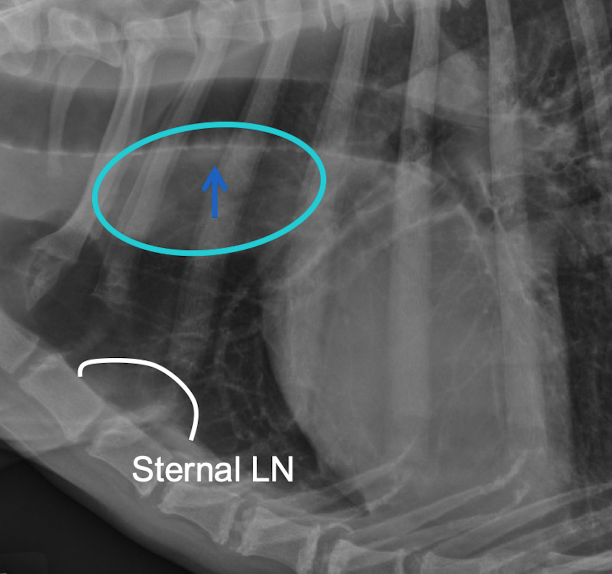

where is sternal lymph node on xray

usually dont see- are swollen in this xray- can drain into the abdomen